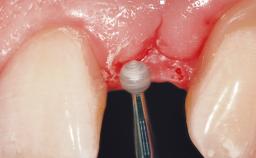

Implant Placement with Simultaneous Contour Augmentation using GBR

The video demonstrates implant placement using a surgical stent according to the principle of prosthodontically driven implant placement. The deficient ridge is augmented with locally harvested autologous bone chips, a superficial layer of xenogenic DBBM particles and a resorbable collagen membrane. The surgery is completed with a precise, tension-free primary wound closure.